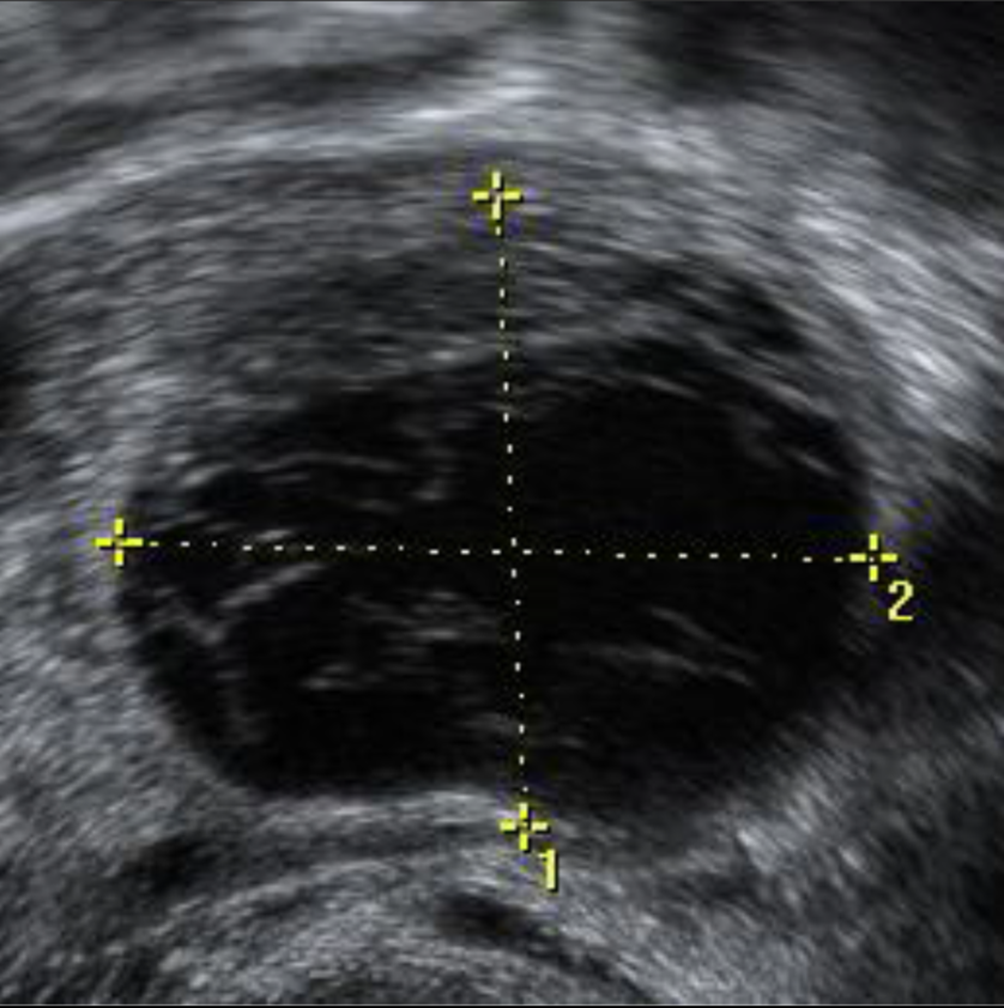

Abb. 2

Die Einblutung in das Corpus luteum fällt als Serie von parallel angeordneten, dünnen, leicht echodensen Streifen auf, die auf das echodensere Fibrin zurückgeführt werden (Größe des CL 22 × 18 mm)